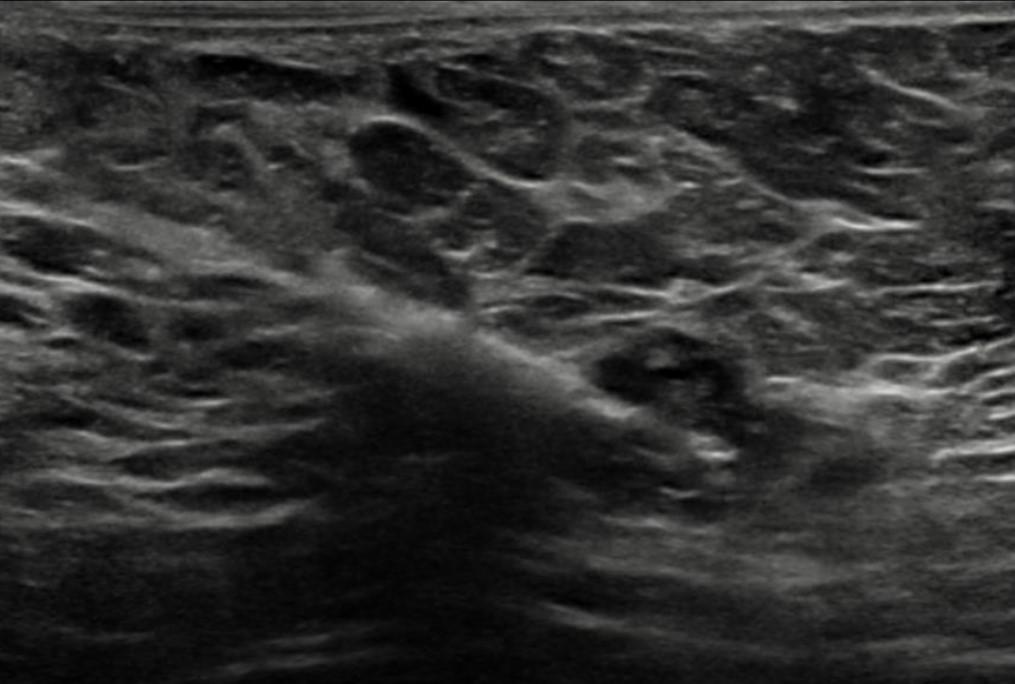

右侧腋窝超声检查可见一个边界清晰的复杂异质性肿块,内部可见小囊性成分以及脂肪回声区域(图8、9、10)。针对这些腋下肿块,建议进一步活检评估。